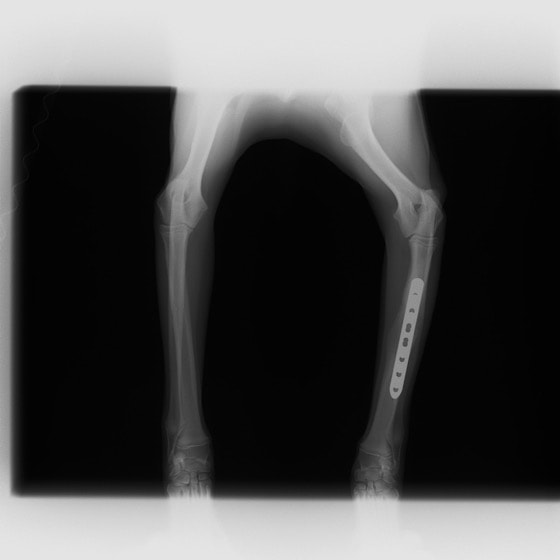

トイプードル 右遠位橈尺骨短斜骨折のALPSによる内固定

LCPは、スクリュー(ネジ)とプレート(金属の板)をロックする特殊な構造により骨折部位を固定する新しい世代のプレートシステムです。ひとつのホールでロッキングスクリューとスタンダードスクリューの使用を選択できるユニークな構造をしているため、骨折断端間の圧迫を目的とした従来型プレート固定法に加え、高い角度安定性を有するロッキングスクリューを用いた固定法の選択が可能です。従来のプレートシステムでは困難だった部分の骨折や癒合不全の症例に高い治療効果をもたらします。

当院ではAdvanced Locking plate system(ALPS)と、Locking compression plate system(LCPS)という骨接合法で骨折症例の治療を行っています。